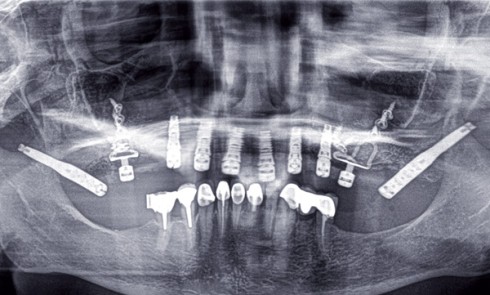

Article réservé à nos abonnés Chronologie du plan de traitement : paro, ortho, implanto

Depuis les travaux de Brånemark, l’implantologie moderne basée sur les données scientifiques offre une option thérapeutique fiable à long terme....